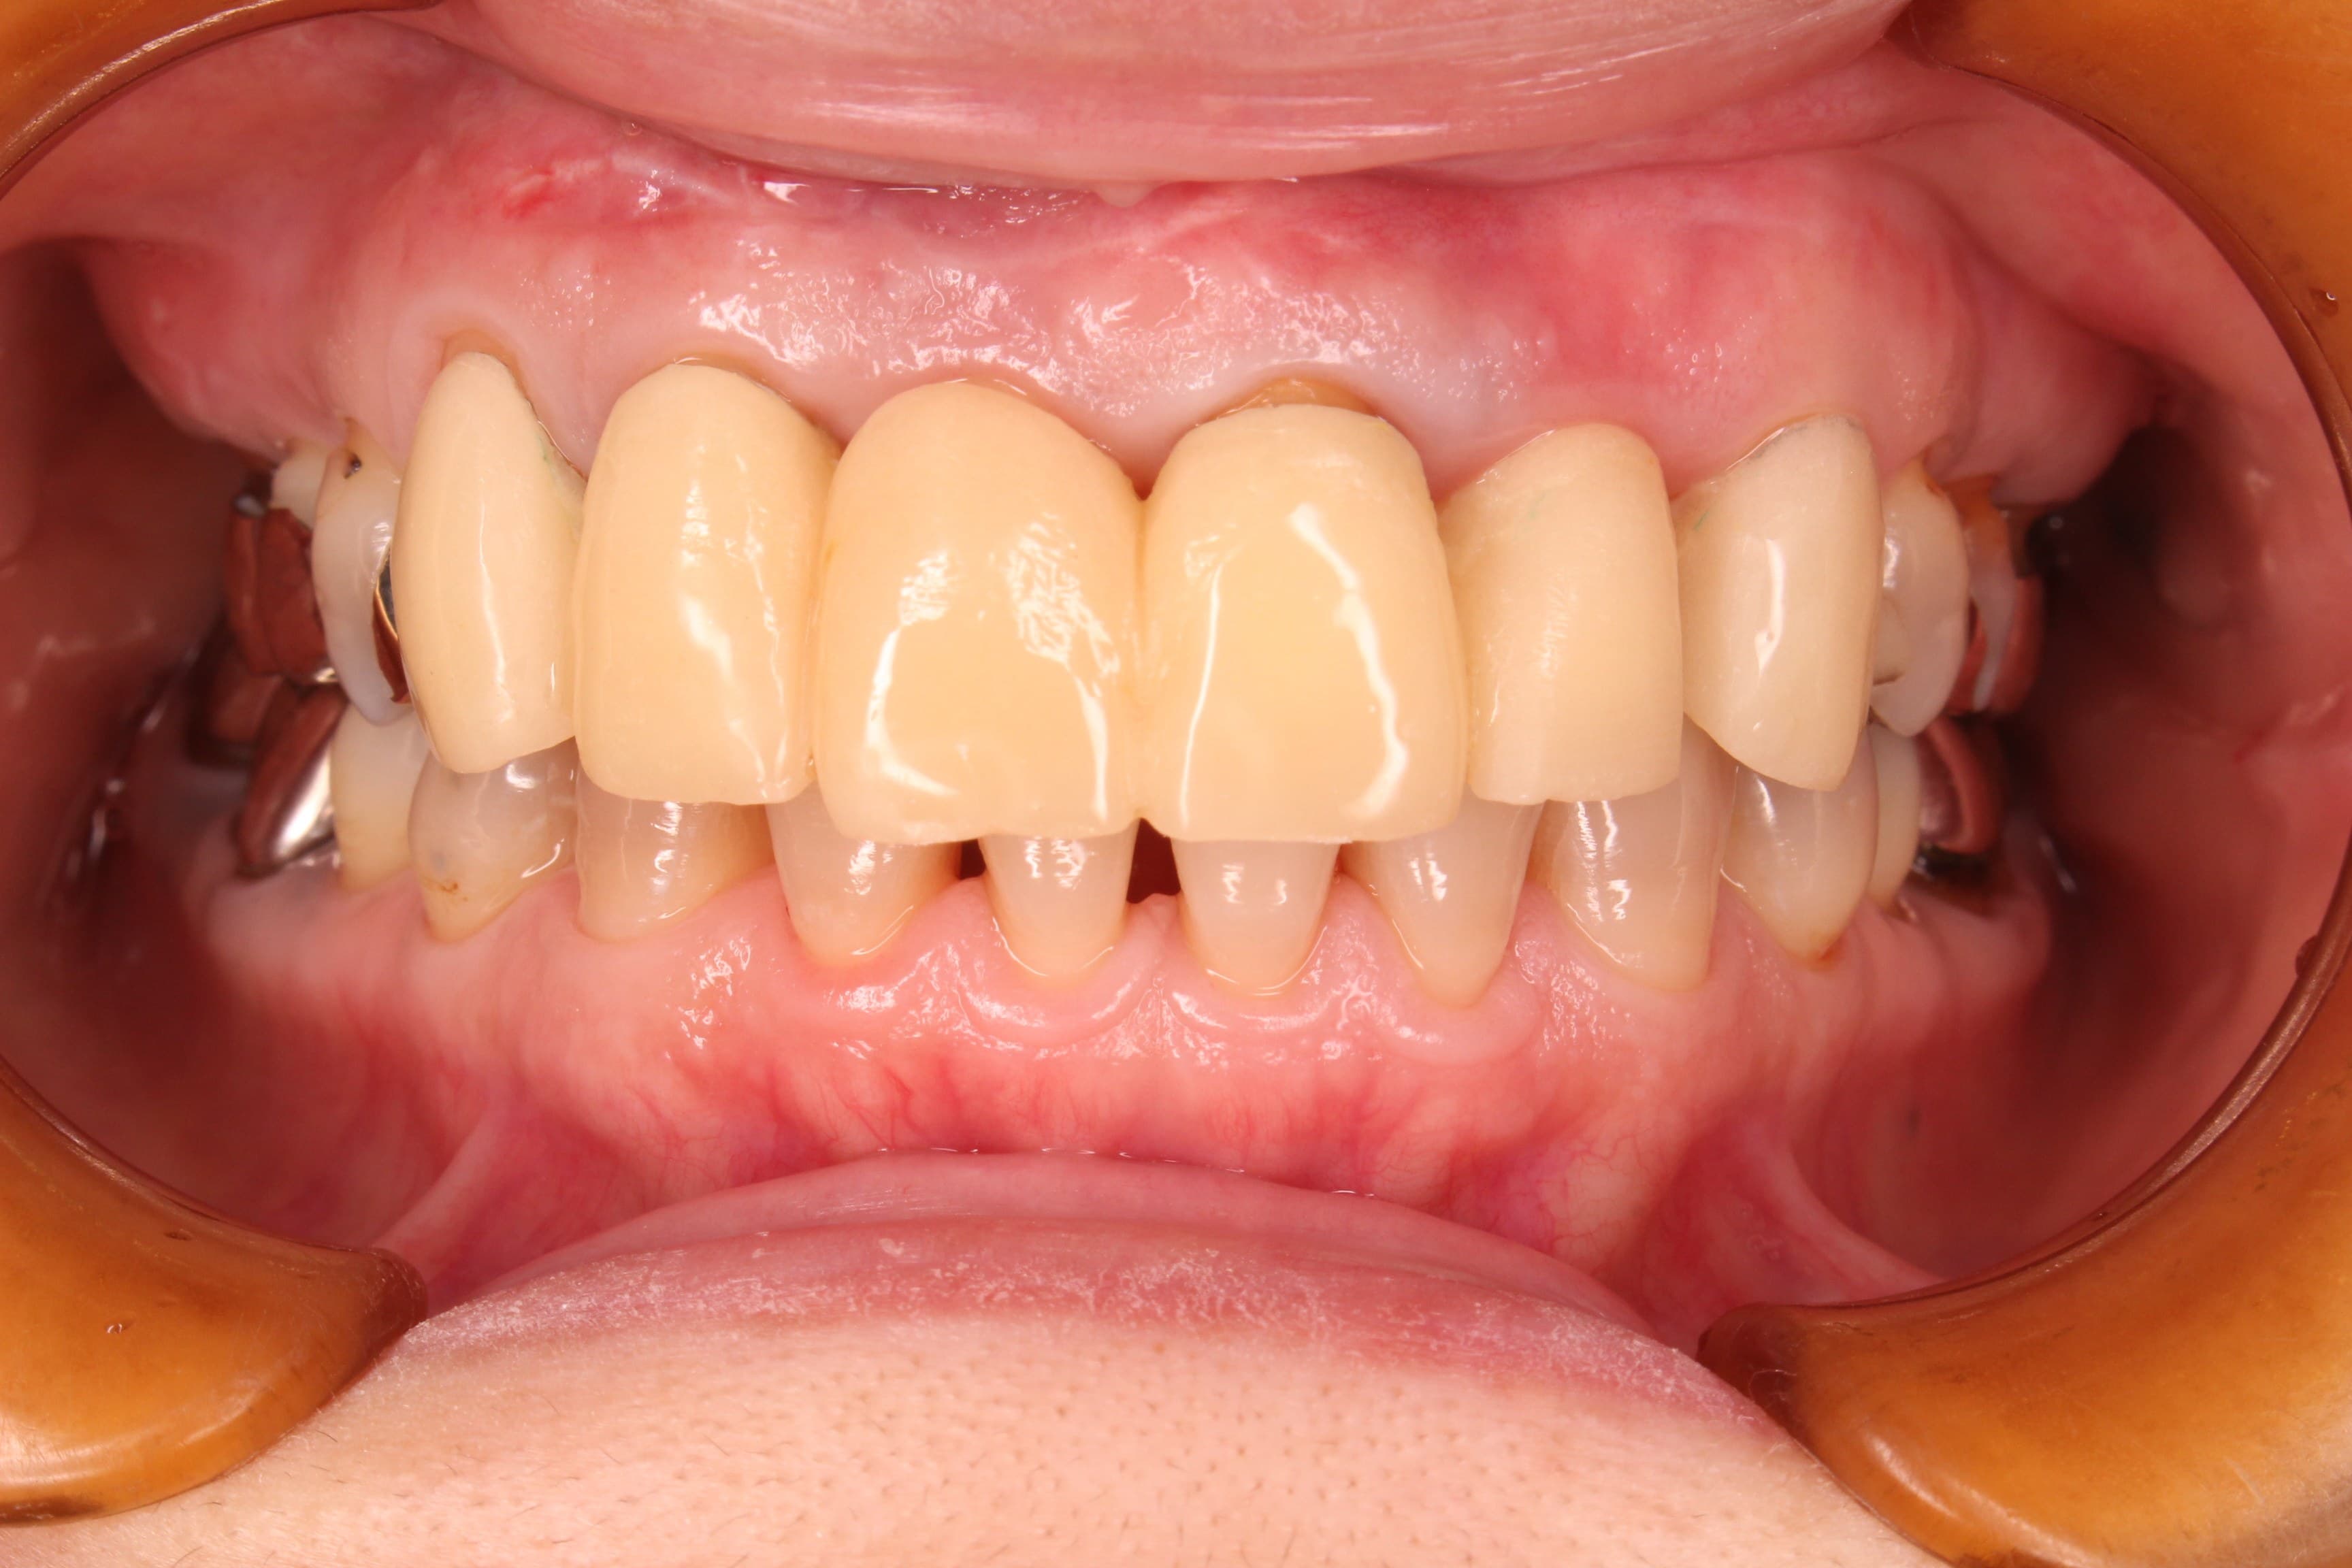

今回ご紹介する歯周専門治療のケースは、50代女性の方です。

歯ブラシを当てると出血するような状況だった為、当初は血がブラシに付くと磨く事に消極的になっていましたが、段々と良くなっていく実感をご自身で感じて頂けた事で、歯周病の治療後は見違える程、症状が改善しました。

ご自身でも、良くなったことを実感して頂けて本当に良かったと思います。

(上記の写真は1回目の仮歯を入れて撮影したものです。)